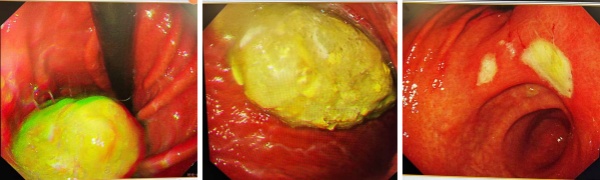

李**,女性,66岁,1天前进食大量山楂后出现胃痛恶心。左图胃镜提示胃石,右图为该患者因胃石压迫形成的溃疡照片。

王**,女性,65岁,4天前进食大量山楂后出现胃痛恶心呕吐。胃镜提示胃石及溃疡。